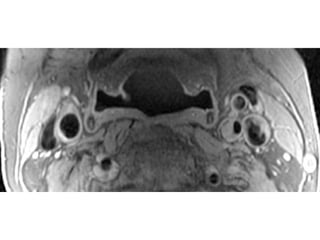

The document describes the Pathway MRITM Carotid Array coil, which is designed for high resolution imaging of small soft tissue structures like the carotid arteries. It provides images showing atherosclerotic plaque buildup in the carotid arteries, including plaque in the common carotid artery, carotid bifurcation, and internal carotid artery stenosis and plaque.